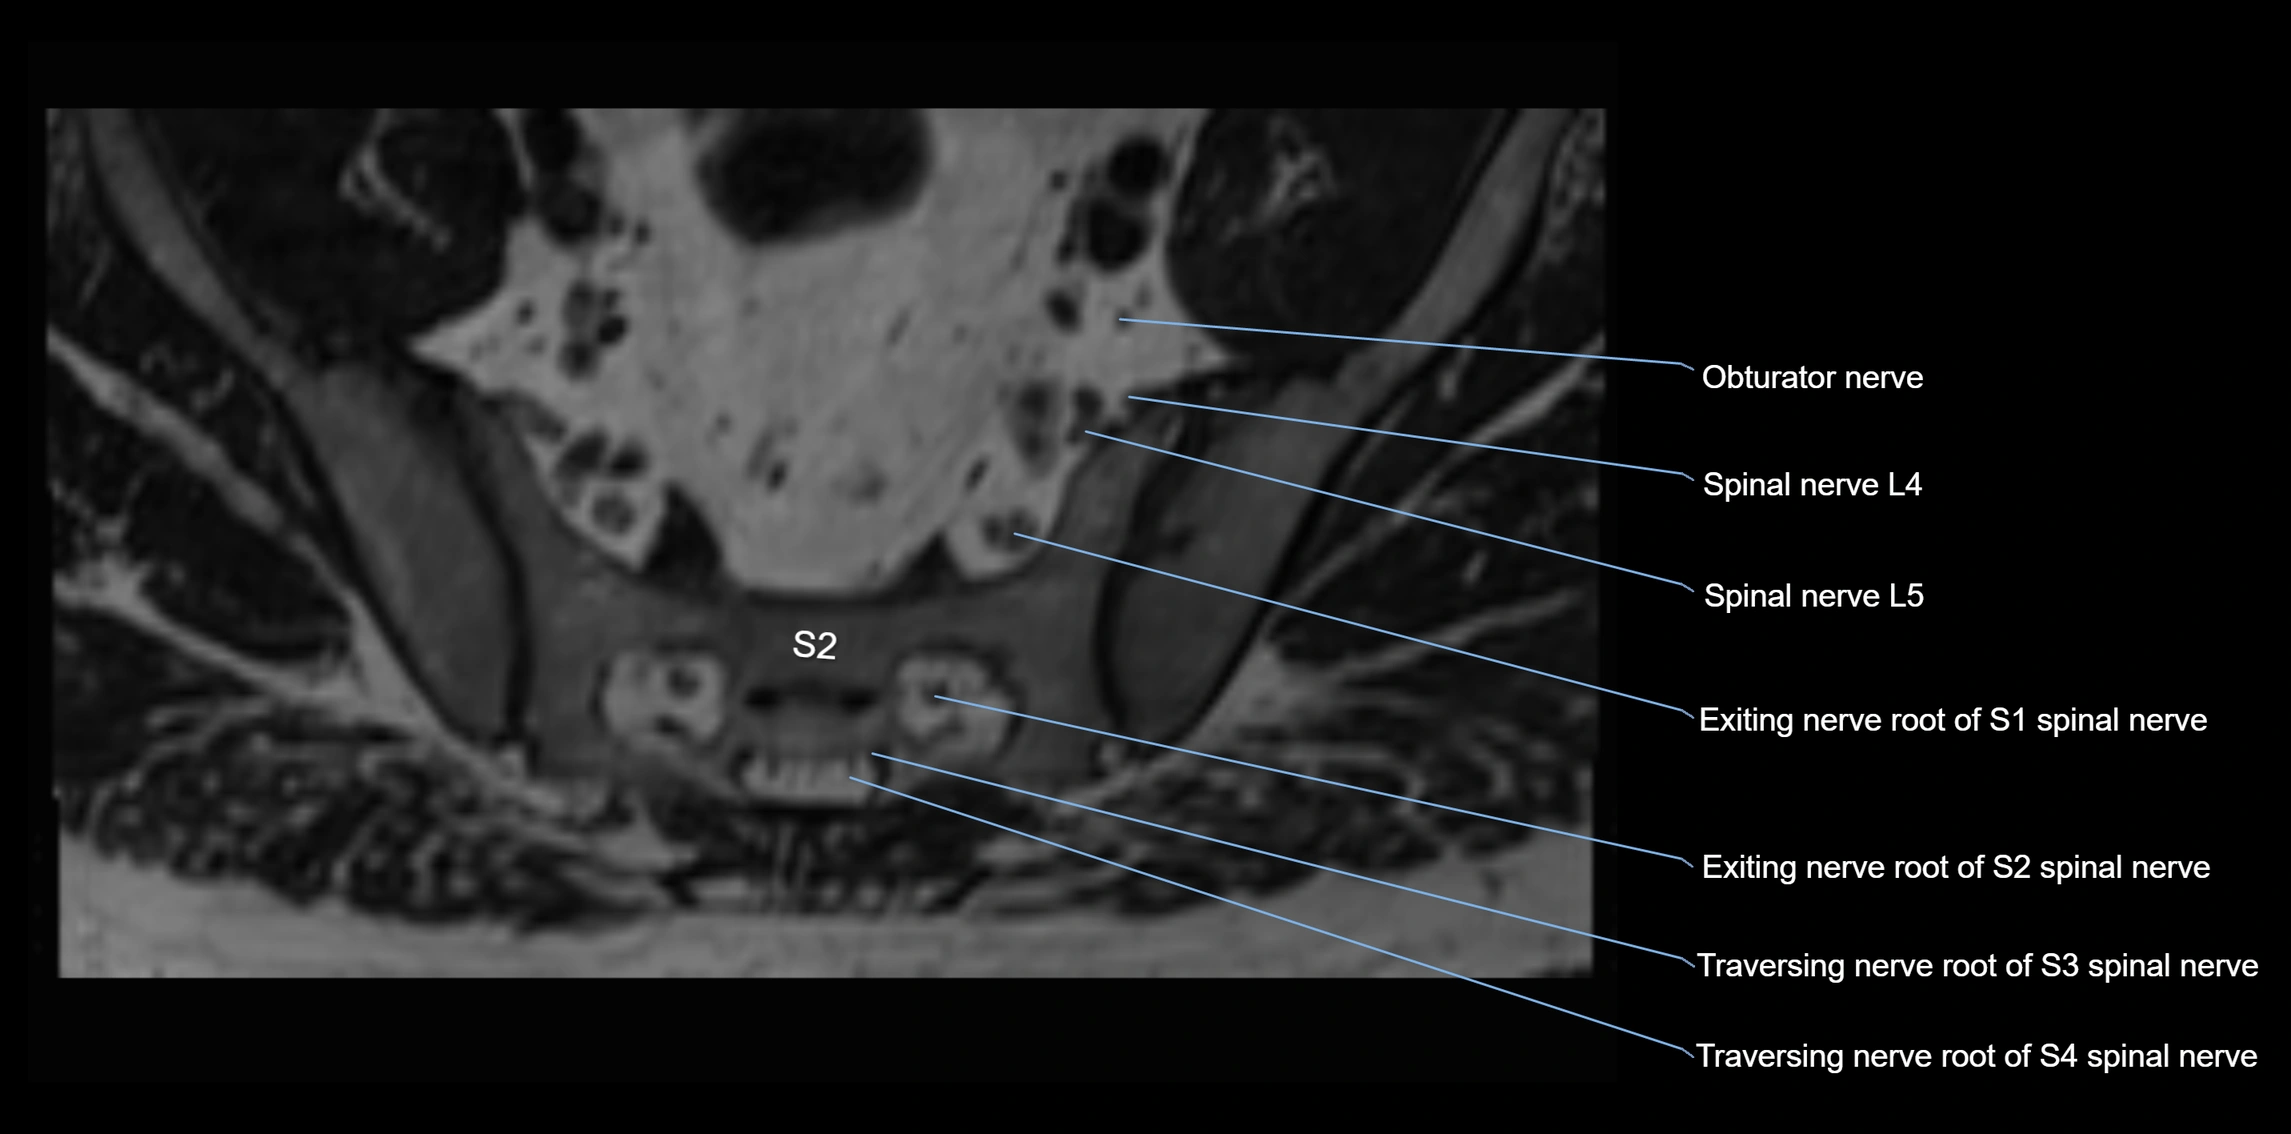

MRI image

image